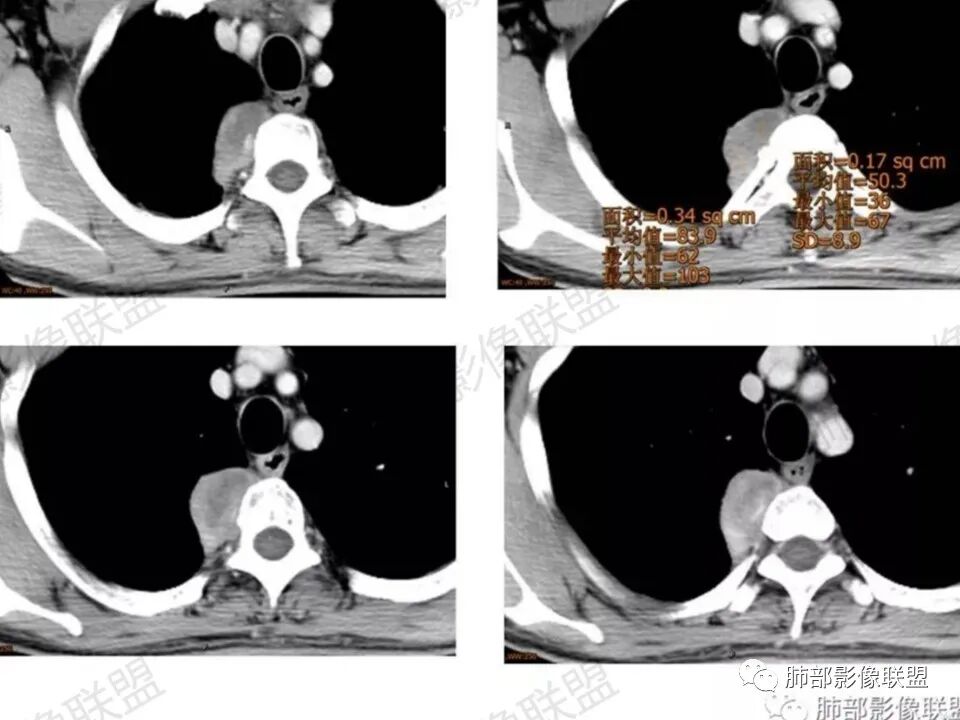

AF在CT及MR上的密度、信号取决于并各种成分的比例和分布,导致密度、信号及强化不均匀。

CT上密度呈稍低密度区,MR上与肌肉相比T1W呈稍低信号,T2W呈稍高信号,增强后渐进性强化。

胶原纤维

CT上呈稍高密度,MR上呈T1W、T2W均为低信号,增强后病灶不明显,延迟扫描略轻度强化,CT上病灶平扫呈稍高密度,强化后不明显或轻度强化,呈相对低密度改变,呈密度“反转”现象。

粘液、血管成分

梭形细胞容易粘液变性,CT上密度呈稍低密度,MR上T1W呈稍低信号,T2W呈高信号,T2压脂上高信号往往提示粘液成分,增强后延迟略微强化;由于肿瘤较大,需要血供,并且肿瘤呈浸润性生长,生长过程中会将周围血供包绕进去,所以肿块内及周围可见供血血管。

为什么梭形细胞肿瘤为渐进性强化,粘液跟胶原纤维延迟会轻度强化?

由于肿瘤存在“旋涡状”排列的梭形细胞及细胞外胶原纤维,造成对比剂“易进难出”,大量存在于细胞外间隙,使得随时间延迟肿瘤呈渐进性强化、范围扩大,细胞成分较多的区域强化明细,胶原纤维及粘液区成分较多的区域强化较弱,肿瘤内部显著扩张的裂隙状血管可能是肿瘤延长强化的病理学基础,还有粘液会阻碍对比剂的灌注,强化峰值会延长;而且粘液吸附性比较高,会影响对比剂的早期吸收。

这个病例定位肺外没问题,病灶呈宽基底,见明显的胸膜掀起征,定位胸膜或右后纵隔来源,而且肿块提示肋间动脉穿行,脏层胸膜来源可能性不大(脏层胸膜由肺动脉及支气管动脉供血),那就是壁层胸膜跟纵隔来源,但是图像上有2个层面是胸膜外间隙有受压推移,所以壁层胸膜来源也不考虑;病灶是渐进性强化,常见的就是间叶来源含有梭形细胞的软组织肿瘤跟后纵隔常见的神经源性肿瘤鉴别,那如何在后纵隔的大山里拨开云雾找到我们想要的答案呢?那小编在这里先理出几个问题:

问:为什么该病例只提供了增强,没有提供平扫?                         答:咨询了提供病例的於老师,他告诉我因为患者主管医生直接开的是单纯增强CT,故没有做平扫,所以不能观察到CT上所谓的胶原纤维的“反转”现象,而且没有平扫,增强后的无强化或弱强化区不能明确区分是胶原纤维或粘液区,但是MR上有帮助,粘液水分含量高,T2W及压脂序列呈高信号,而胶原纤维T1W、T2W均呈低信号 。

问:这个病例病灶确实邻近椎间孔生长,除了神经源性肿瘤会向椎间孔方向生长,还有什么肿瘤会有这种行为?这个病灶整体形态呈扁平不规则,周围骨质未见破坏,就一定是良性吗?    答:这个病灶明显嵌入式生长,往往提示病灶柔软或有侵袭性,而神经鞘瘤往往有包膜,有张力,典型的形态往往呈类圆形、“逗点形”或“哑铃型”横向延入某一椎间孔内;神经节细胞瘤虽然可以比较柔软,但是具有大量粘液基质,动静脉期强化不明显,延迟强化轻度增强,加之没有钙化,故符合点不多;此外比较柔软的肿瘤如淋巴瘤,但是周围没有肿大淋巴结不太考虑;本例形态不规则的实性肿块,没有明显骨质破坏,倾向具有侵袭性的间叶来源的肿瘤。